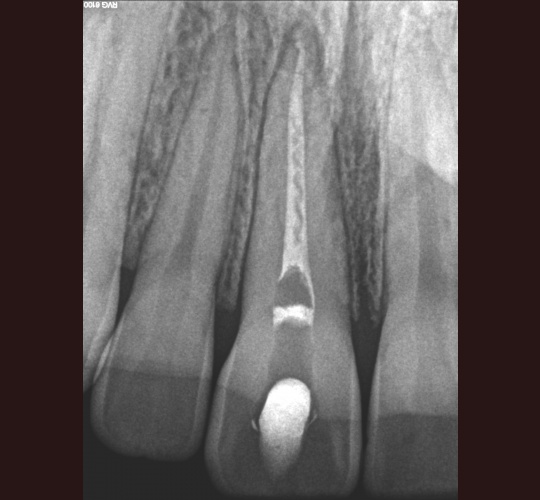

Internal Bleaching: Case #1

Posted in Internal Bleaching